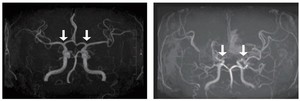

[메디컬프라임 주형준 기자] 소아 모야모야병 조기 진단 가능성을 높이는 새로운 바이오마커가 발견됐다. 모야모야병 환자의 뇌척수액에서 ‘SLITRK1’ 단백질 발현이 유의미하게 높은 것으로 나타났다.또한 뇌경색, 수술 예후 등 모야모야병의 임상 특성과 연관된 단백질도 확인돼, 난치성 질환인 모야모야병 치료에 새로운 패러다임을 제시할 것으로 기대된다.소아 모야모야병은 뇌로 혈액을 공급하는 혈관이 특별한 원인 없이 점차 좁아지는 만성 진행성 뇌혈관질환이다. 이 질환이 있으면 부족한 혈류를 보충하기 위해 비정상적인 미세혈관이 형성되는데,